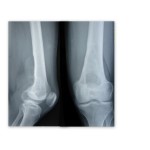

Image of the Month- January 2012

A swelling in the popliteal fossa Authors: Tarun Goyal, Trust Registrar, Victoria Infirmary Hospital, Glasgow , UK Sujit Kumar Tripathy, Clinical fellow, Southtees Hospital NHS Trust. UK Q: A 22-year-old male presented with pain and gradually increasing swelling on the back of the knee for 6 months. He was a known case of haemophilia. There […]